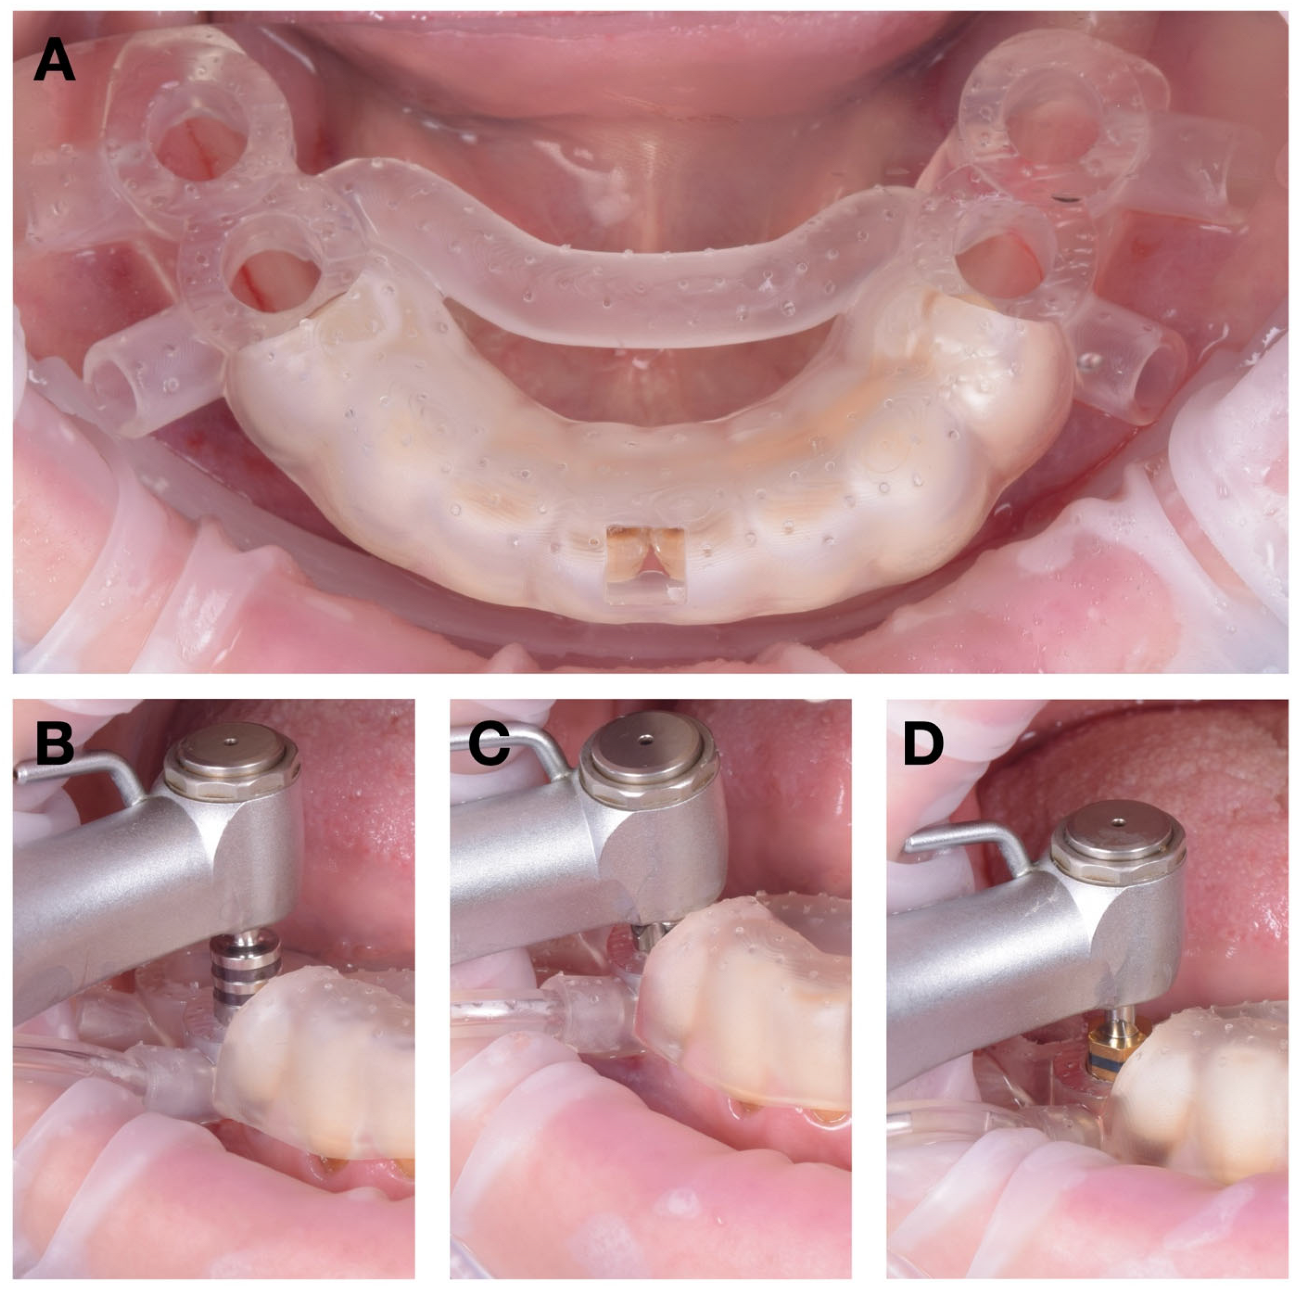

First, the fixation pin insertion guide—replicating the maxillary denture base—was positioned in occlusion and centered along the midline (Figure 8A). Once its stability was confirmed, two holes were drilled through the pin guides at 300 rotations per minute (rpm) under continuous irrigation.

After preparing the fixation sites, the stabilization guide was removed and replaced with the main surgical guide (Figure 8B). The guide was anchored using two fixation pins (Neodent, Curitiba, Brazil), providing rigid three-dimensional stability throughout the subsequent drillings.

The physiodispenser irrigation tubing was connected to the guide’s lateral input port, directing saline solution at approximately 23 °C through the internal channels toward the osteotomy site. This setup ensured continuous laminar cooling during each drilling sequence. Osteotomies were performed in accordance with the manufacturer’s protocol for DENTIS SQ implants, and the four implants were inserted according to the digital plan (Figure 8C–E).

We next proceeded to the posterior mandibular implant placement. A tooth-supported internally cooled guide was used (Figure 9A), stabilized by occlusal contact with the remaining dentition. This design allowed accurate transfer of the digital plan while maintaining full visibility and irrigation control during surgery.

Four implants were inserted in positions 35–36 and 45–46 in accordance with the initial plan. All osteotomies were performed under continuous internal irrigation through the integrated channels, which maintained a constant saline flow at 23 °C to the drilling site (Figure 9B,C).

After implant placement, primary stability values exceeded 35 N·cm, confirming optimal bone quality and torque conditions for healing screws (Figure 9D).

Figure 8. Surgical sequence for maxillary implant insertion: (A) drilling the pin holes with the stabilization guide in occlusion; (B) fixing the maxillary surgical guide in position with pins; (C) cutting the mucoperiosteum using the mucotome; (D) guided drilling; (E) implant insertion.

Figure 9. Surgical sequence for mandible implant insertion: (A) positioning the surgical guide over existing crowns; (B) cutting of the mucoperiosteum using the mucotome; (C) guided drilling; (D) implant insertion.